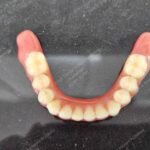

C1005 zygomatic basal implant full mouth – Ali Hasan 4

Dr. N.B. Singh